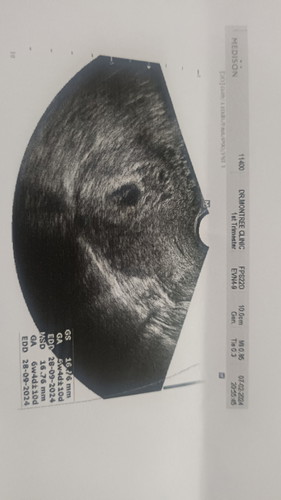

ประจำเดือน วันสุดท้ายวันเดียวกันเลยค่ะ ของหนูหมอก็บอกท้องลม ให้เน็บยาออก แต่เลือกที่จะไม่เน็บค่ะ ทั้งที่เลือดออกทุกวัน 17 วันเต็มๆ ล่าสุดลองเปลี่ยน รพ ค่ะ หมอซาวให้ล่าสุดคือภาพนี้ หมอบอกถุงสวยกลมขึ้น ใหญ่ขึ้น รอติดตามอาการ นัดอีก1อาทิตย์มาซาวใหม่ค่ะ

ลองเปลี่ยนหมอดูก่อนนะคะ บ้านนี้ถ้านับตามประจำเดือน 11 สัปดาห์แล้ว แต่ไปอัลตร้าซาวมาเมื่อวานหมอบอก 6.6 สัปดา นัดซาวใหม่อาทิตย์หน้า หมอบอกแม่ว่ารอได้นานถึง 16 สัปดาห์ เพราะแม่ไม่มีเลือดออก แม่ก็จะรอไปเรื่อยๆค่ะ แต่ก็จะไปซาวที่อื่นเพิ่มด้วยค่ะ

ยังไม่เจอหัวใจค่ะ